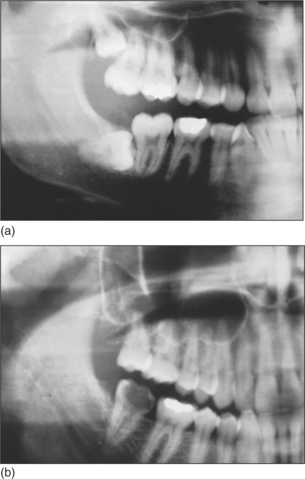

The maxillary sinus is often referred to as the maxillary antrum (or more simply the ‘antrum’). It is important to the dental surgeon because of its close relationship to the posterior maxillary teeth (generally from first premolar to third molar). The proximity varies between individuals (Fig. 15.1) but tends to increase with age as the antrum enlarges. The antrum can encroach into alveolar bone after tooth extraction, and periapical bone loss resulting from dental disease may further decrease the amount of bone separating it from the teeth. This close anatomical relationship can lead to diagnostic difficulties because both the antrum and the maxillary teeth are innervated by branches of the maxillary division of the trigeminal nerve. In addition, infection may spread from the periapical region of the posterior maxillary teeth to the antrum (and in the opposite direction) and the antrum is at risk of iatrogenic damage during certain dental procedures.

Fig. 15.1 (a) A small maxillary antrum that does not reach the apex of the second premolar. (b) A large maxillary antrum that reaches to the apex of the lateral incisor.